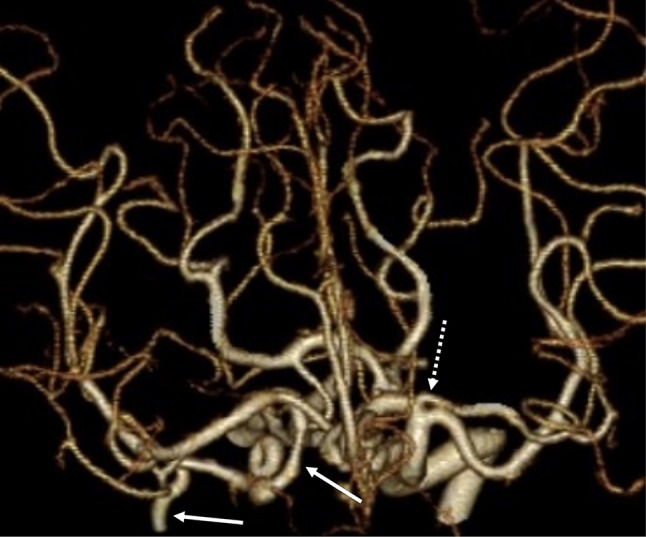

Purpose: To describe a case involving congenital absence of the right common carotid artery (CCA) associated with a left accessory middle cerebral artery (MCA) that was diagnosed by computed tomography angiography (CTA).

Methods: A 63-year-old woman with a narrow right internal carotid artery (ICA) incidentally detected on magnetic resonance imaging underwent CTA for further vascular evaluation.

Results: CTA revealed absence of the right CCA, with the right external carotid artery (ECA) branching from the brachiocephalic trunk and the right ICA branching from the right subclavian artery. The ICA was hypoplastic. A left accessory MCA was also observed. Although blood flow in the right ICA was decreased, the patient was asymptomatic; thus, conservative treatment was administered, and her clinical course remained uneventful.

Conclusion: Absence of the CCA is associated with the development of the aorta and various vascular variations; however, to our knowledge, this is the first report of an association with a contralateral accessory MCA, the existence of which may be considered incidental. Preoperative knowledge of this rare variation is important when considering endovascular treatment of cerebral aneurysms and other arterial lesions.